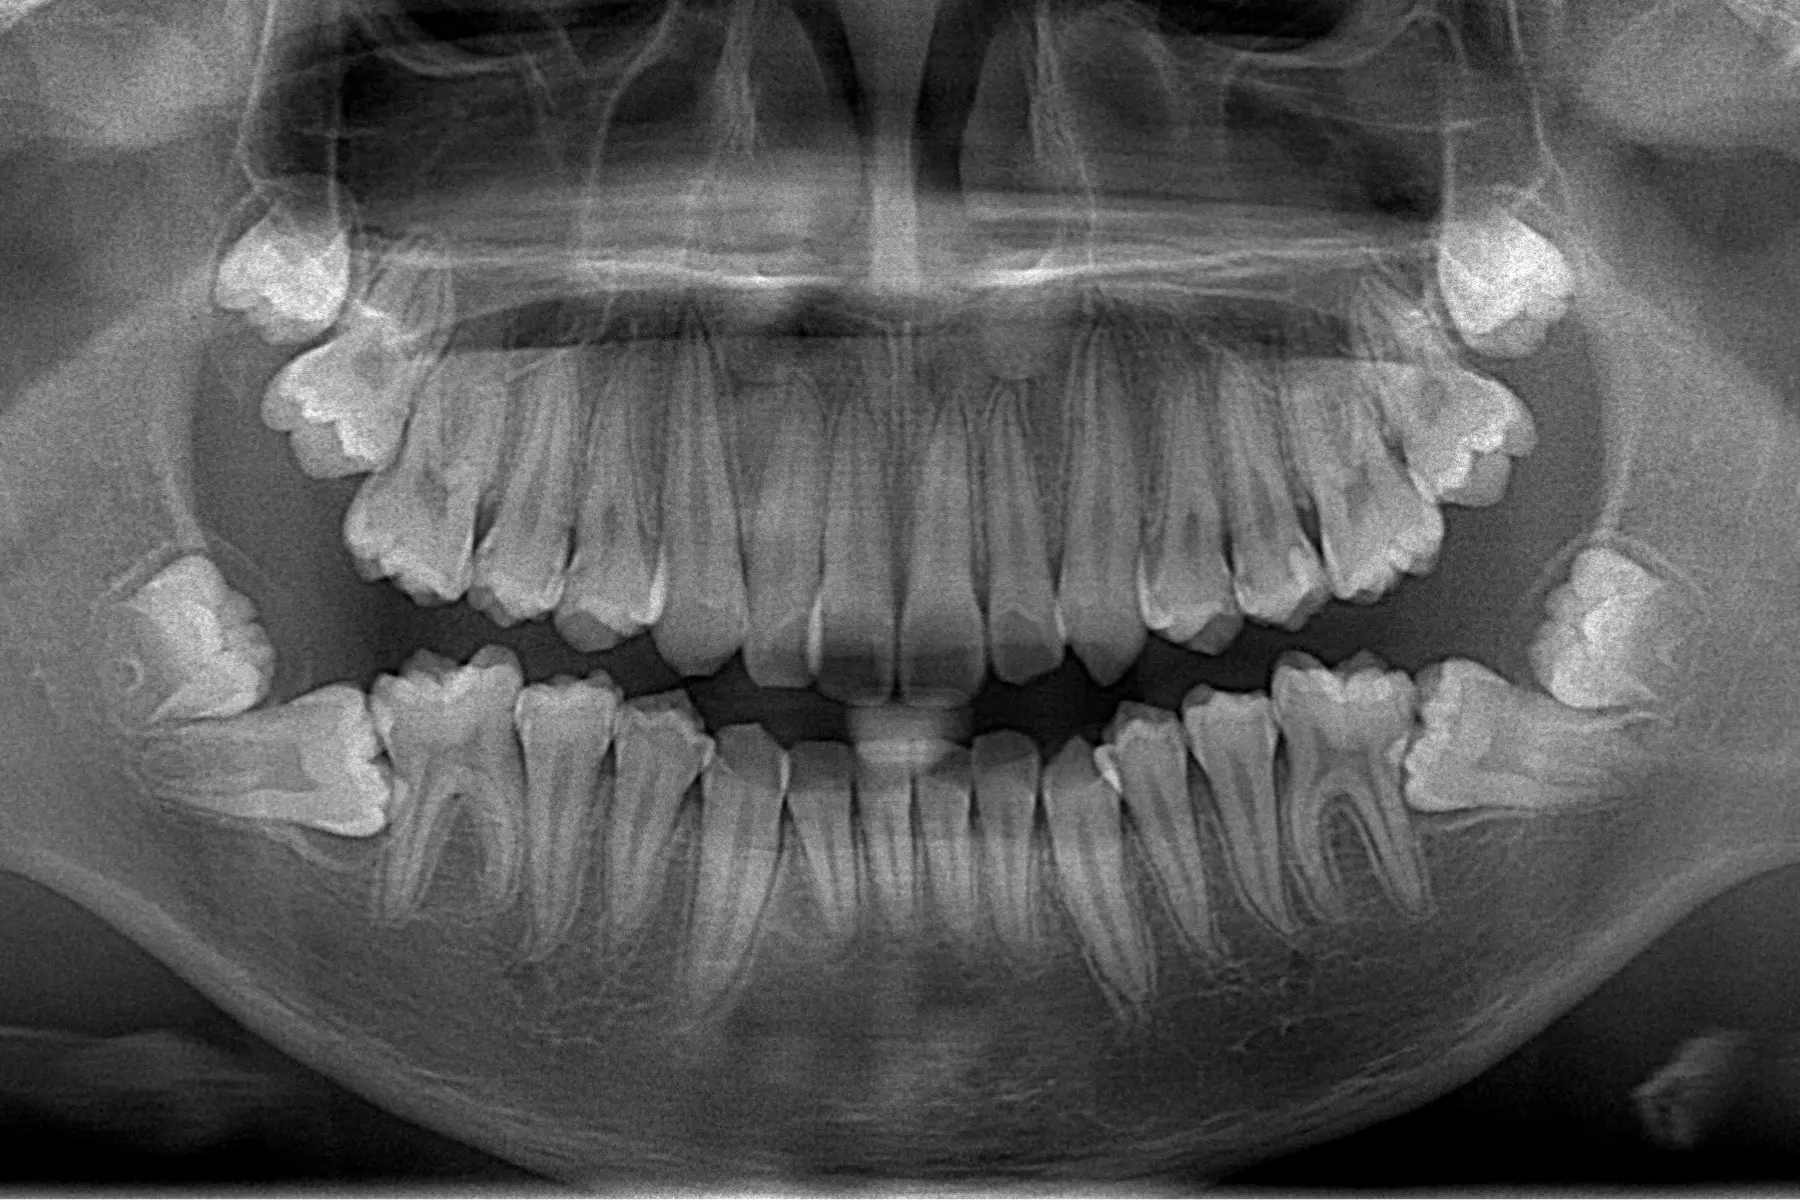

進行牙齒矯正,首先要先明白確定自己的困擾在哪裡,清楚瞭解自己的期望和需求是什麼,初次就診時,為了取得您全口的健康狀況,會先拍攝口內及口外數位照,環口 X 光片及側顱 X 光片,使用iTero element 5D 口掃,取得口腔內的3D模型,觀察目前的牙齒與口腔狀況並讓您了解目前的牙齒狀況,告訴您簡單的治療方向並會展示類似的案例及作法,讓您得知矯正後預見的變化,也會依據您的狀況為您量身打造適合的矯正療程方案!